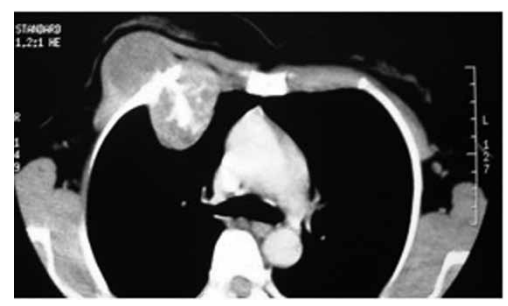

Paciente 45 anos, com abaulamento em região torácica

anterior há 2 anos. Exame físico: lesão endurecida, pouco móvel, pouco dolorosa, em região anterior de hemitórax direito.

Tomografia de tórax a seguir:

(Arquivo pessoal; imagem usada com autorização)

Biópsia demonstra: hipercelularidade, condrócitos com núcleos volumosos e as vezes binucleados, polimorfismo, atipias, matriz celular mixoide, invasão e destruição de trabéculas ósseas adjacentes.

O diagnóstico do paciente é de